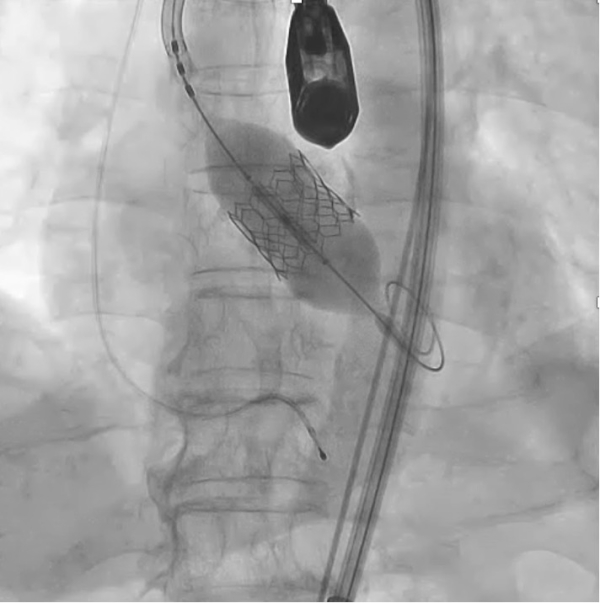

TAVI弁留置

最先端デバイスを手に取り、自分の手で大動脈弁を留置する貴重な一瞬。目の前で動くリアルな解剖モデルを相手に、確かな手応えと自信を得られます。